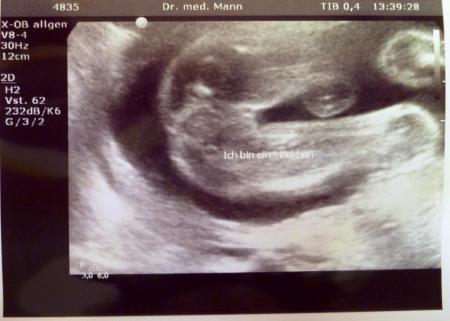

Hallo Mädels, ich war heute nochmal bei meinem FA ... letzten Mittwoch hat das Ultraschallgerät gestreikt und ich durfte heute nochmal kommen. Zuerst hat die Maus geschlafen und wollte sich nicht zeigen. Sie hat ihre Arme verschrenkt vors Gesicht gehalten - "Hey, nicht gucken. Ich möchte schlafen!" Nach längerem Warten und rütteln des Schallkopfes hat sie sich doch noch bewegt und ihr Gesicht gezeigt. Und ein erneuter Blick zwischen die Beine bestätigte nun zum dritten Mal das Outing - Mädchen, nun auch mit Beweisfoto! Viele Grüße, Claudia

Total schöne Bilder! Echt süß wie sie die Arme verschränkt hält! Herzlichen Glückwunsch dass es auch weiterhin und nun endgültig beim Mädchen bleibt!!!